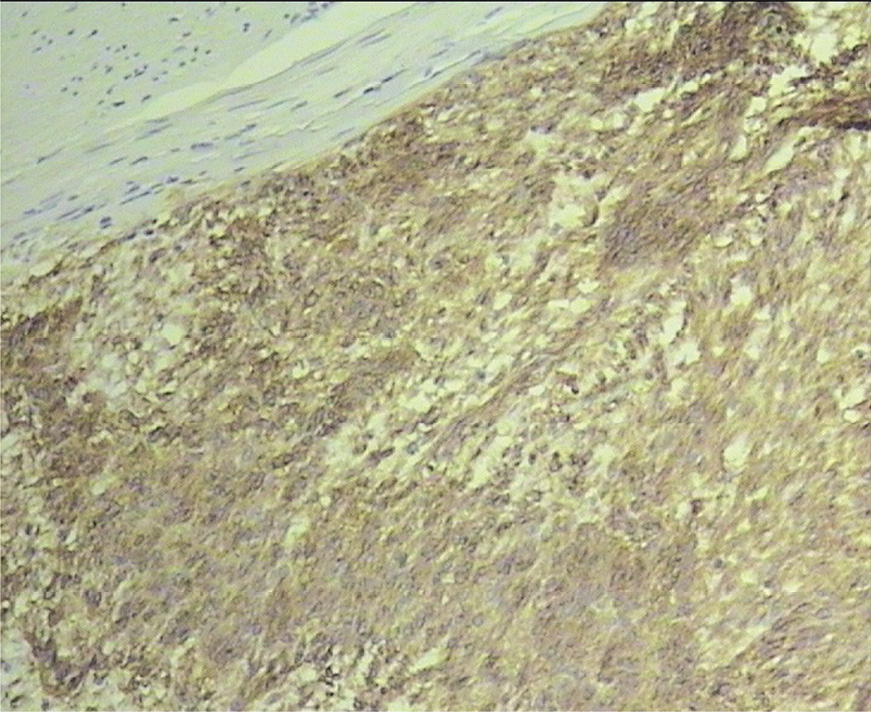

При иммуногистохимическом исследовании в клетках опухоли выявлена экспрессия виментина (+++), c-KIT (+++), CD34 (++), гладкомышечного актина (++), S100 (++); отсутствовала экспрессия десмина, CD57, GFAP. Индекс пролиферации опухолевых клеток по экспрессии Ki-67 составил 12–15% (рис. 5).

Рис. 5. Первичная ЭГИСО. Иммуногистохимическое исследование. Экспрессия CD117, ×100.